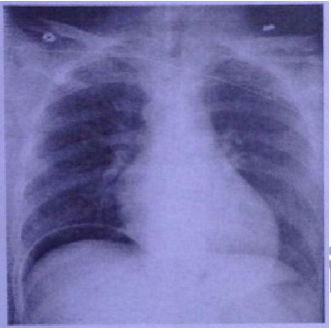

Paciente masculino de 65 anos de idade foi submetido à gastrectomia total por causa de adenocarcinoma gástrico em pequena curvatura. Tinha antecedentes de hipertensão arterial sistêmica usando losartana 50 mg/dia e diabetes mellitus não insulino- dependente e controlado com metformina 500 mg 2X dia e dietoterapia. Estava evoluindo satisfatoriamente nos dias subsequentes. No 4º dia de pós-operatório evoluiu com febre e dor abdominal difusa, apresentou-se ao exame físico com FC: 124 bpm, FR: 28 irpm, temperatura axilar de 39º C e pressão arterial de 80/50 mmHg. Ao exame respiratório, apresentava estertores inspiratórios em bases pulmonares com diminuição do murmúrio vesicular. Havia dor à palpação abdominal difusa, presença do sinal de Joubert e descompressão brusca no andar superior do abdome. Os ruídos hidroaéreos estavam diminuídos. Radiografia de tórax realizada durante o quadro: (VER IMAGEM) Em relação ao caso, assinale a afirmativa correta.